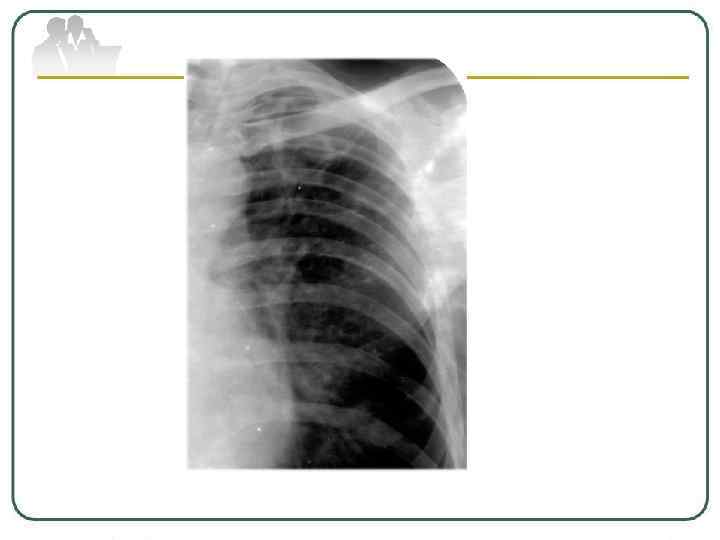

Фиброзно-кавернозный туберкулез легких характеризуется наличием фиброзной каверны, развитием фиброзных изменений в окружающей каверну легочной ткани. Для него характерны очаги бронхогенного отсева различной давности. Как правило, поражается дренирующий каверну бронх. Развиваются и другие морфологические изменения в легких: пневмосклероз, эмфизема, бронхоэктазы. Формируется фиброзно-кавернозный туберкулез из инфильтративного, кавернозного или диссеминированного процесса при прогрессирующем течении заболевания. Протяженность изменений в легких может быть различной; процесс бывает односторонним и двусторонним с наличием одной или множества каверн.